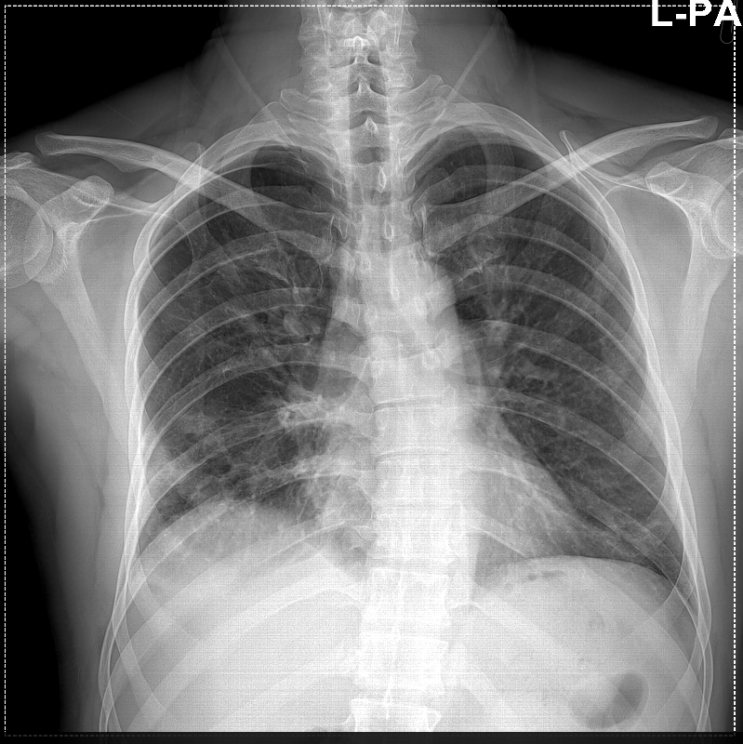

This is my Chest Xray, Is costo visible with these? I have been Is Costochondritis Visible On X Ray costochondritis is typically diagnosed by ruling out other conditions, and there is no specific laboratory or imaging test that can diagnose the. it often goes away on its own after a few days or weeks. Advanced imaging such as cta may be needed to rule out serious. there is no laboratory or imaging test to confirm a. Is Costochondritis Visible On X Ray.